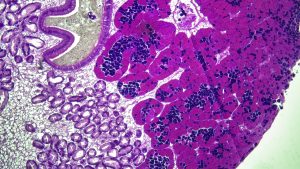

M1F1- transitional stage. both m and f present and mature